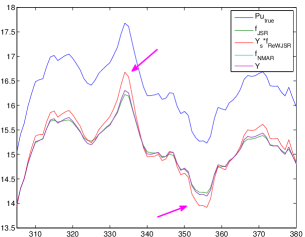

By combining (3.7) with (3.6), the proposed re-weighted JSR model is able to repair the degraded projection so that the repaired data is closer to , where is the Radon domain solution from (3.1) and is the unknown ground-truth CT image. Note that it is hard to obtain the ground truth image for polychromatic energy CT with varying attenuation coefficients with respect to the energy level, we choose the NCAT phantom (Figure 1(a)) as the approximated ground truth CT image . Empirically, the repaired projection data fits the linear inverse problem (1.2) better than the repaired projection data and computed from the NMAR and the unweighted JSR model (3.2) respectively. This is the key to the success of the re-weighted JSR model since the linear model (1.2) is what we commonly assume for CT imaging. Such linear assumption is not correct (though reasonable) for a multi-chromatic imaging system.

To support such claim, we present comparisons of with , , and in Figure 5 using the NCAT phantom. We observe that is a better approximation to the projection of the reference image than the repaired projection data from the JSR and NMAR model (see Figure 5(c),(d)). The NMAR model also generates a better repaired projection than the unweighted JSR model due to its re-weighting strategy. However, the unweighted JSR model is still able to reduce the majority of the metal artifacts in the reconstructed image due to its sparsity based joint regularization. These observations, together with the reconstruction results in Section 4, show that the re-weighted JSR model combines the merits of the NMAR model’s weighting strategy and the sparsity based joint regularization of the unweighted JSR model.

To quantitatively measure the difference between and the repaired projection data from different models and the measured projection data , we calculate the -norms , , and . Since the region of the metal trace has major contribution to these quantities, we also compute the -norms excluding the regions of the metal trace. Results are shown in Table 3. Obviously, the repaired projection data from the re-weighted JSR model is closer to than that from the NMAR and JSR model. However, although is closer to in regions outside of , is overall closer to than due to the inaccurate recovery of the projection data inside the metal trace by the re-weighted JSR model (see Figure 5(c)). This is probably why the re-weighted JSR model still cannot fully remove metal artifacts, though it improves over the unweighted JSR and the NMAR model.